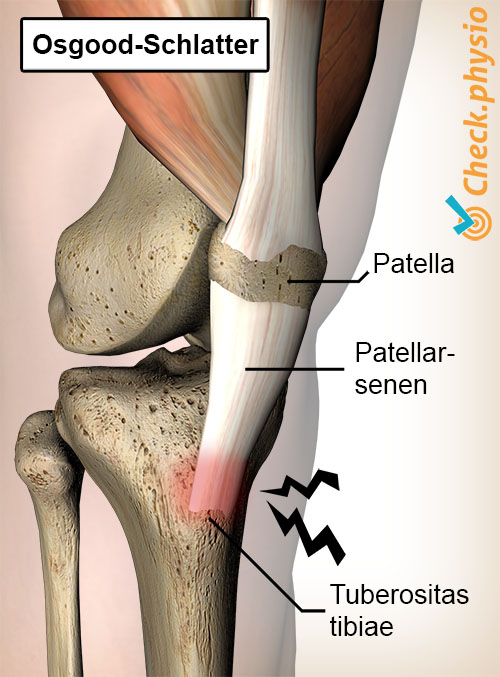

Festet til kneskålens sene på skinnebenet er irritert og betent ved Osgood-Schlatter. På fagspråkkalles dette apofysitt. Dette forårsaker smerte ved festepunktet av kneskålens sene på den harde kulen som ligger rett under kneet på fremsiden. Denne kulen kalles også tuberositas tibiae.

Ofte dannes det etter noen måneder mer beinvev enn normalt på stedet hvor kulen er. Dette skyldes strekkrefter fra senen på beinvevet. Kroppen produserer dermed mer beinvev for å styrke beinet ved seneinnfestningen.

Symptomene starter som regel litt diffust og forverres over tid. Hos barn som fortsatt vokser er kulen ennå ikke helt forbenet. Smerten skyldes den stadig pågående dragningen fra kneskålens sene på den utviklende tuberositas tibiae.